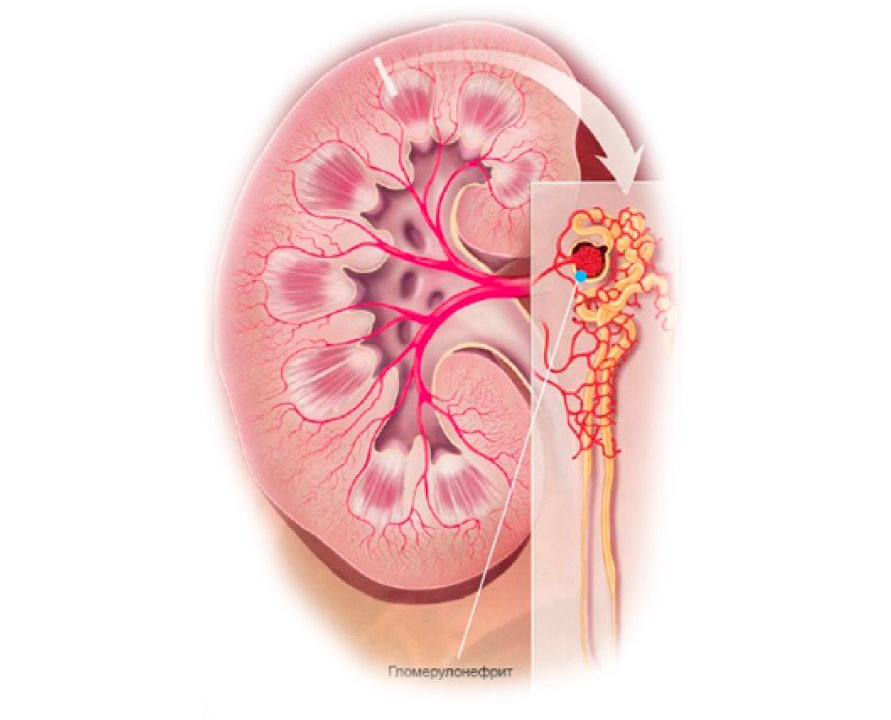

Симптомы подострого гломерулонефрита: фото и описание